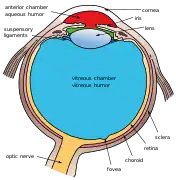

Cross-section of human eye, with choroid labeled at top. | |

Interior of anterior half of bulb of eye. (Choroid labeled at right, second from the bottom.) | |

Schematic cross section of the human eye; choroid is shown in purple.

The interior of the posterior half of the left eyeball Structures of the eye labeled

Structures of the eye labeled This image shows another labeled view of the structures of the eye

This image shows another labeled view of the structures of the eye Calf's eye dissected to expose the choroid: its tapetum lucidum is iridescent blue